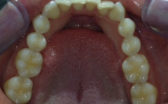

Whilst being fairly happy with my smile, I have always wanted to have perfectly straight upper and lower front teeth. There was some overlap of my upper lateral incisors (the teeth next to the front teeth) over my front teeth. My lower front teeth overlapped each other and were a bit crowded. I did not want to have a long course of braces to correct this, so Cfast sounded like a good option for me.

- Before